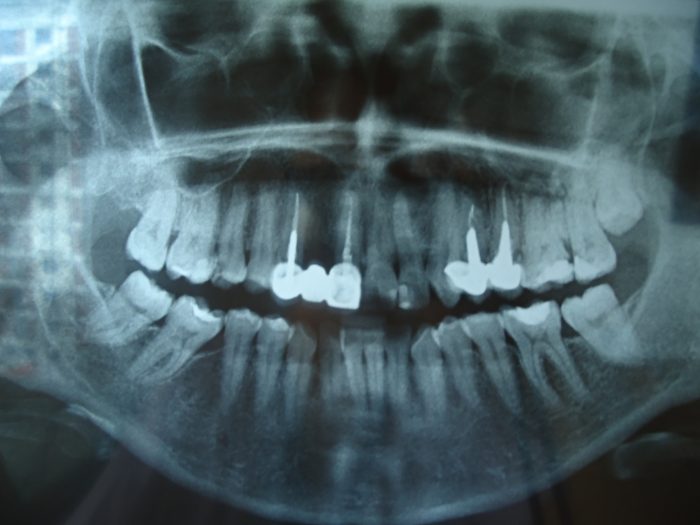

0- rx inicial Se observa puente piezas anterores con ausencia del 1.2 RX inicial. Se observa puente piezas anterores con ausencia del 1.2 Deja un comentarioLo siento, tenés que estar conectado para publicar un comentario.